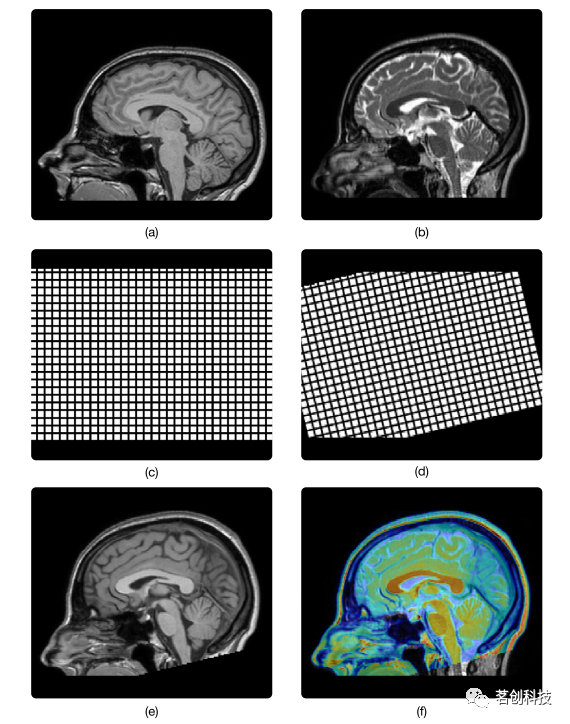

基于变换空间,图像配准算法也可分为刚性配准和非刚性配准。如果一个算法的候选变换是线性的,并且保留了直线段的长度,则认为该算法是刚性的;这种保持长度的线性变换称为刚性变换。刚性图像配准通常用于被试内的应用,当预期大小和形状无差异时,以校正相同被试图像之间的位置和方向差异,例如运动校正。图1d通过其在图1c所示的规则网格上的作用说明了刚性变换的效果。如果一个算法的候选变换是非线性的,则认为该算法是非刚性的;这种变换称为非刚性变换。非刚性变换包括所有可变形变换和非刚性线性变换。

图1.被试内配准的图像融合示意图。图(a)和(b)显示了健康个体的T1加权(T1w)和T2加权(T2w) MRI脑部扫描。几何变换可以用一个规则的网格来可视化,如图(c)所示,应用变换后的相同网格,如图(d)所示。图(e)显示了应用这个变换后的T1w扫描,现在与T2w扫描对齐。图(f)所示实现了来自同一被试的两种不同对比的融合。